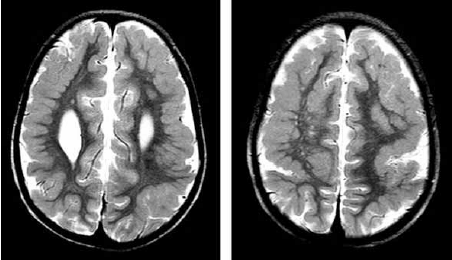

Paciente com atraso global do desenvolvimento e epilepsia. Na investigação foi realizada a ressonância magnética de crânio a seguir.

A achado de imagem sugere